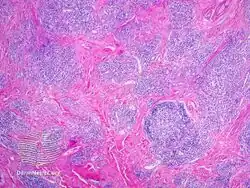

IgG4-related skin disease pathology